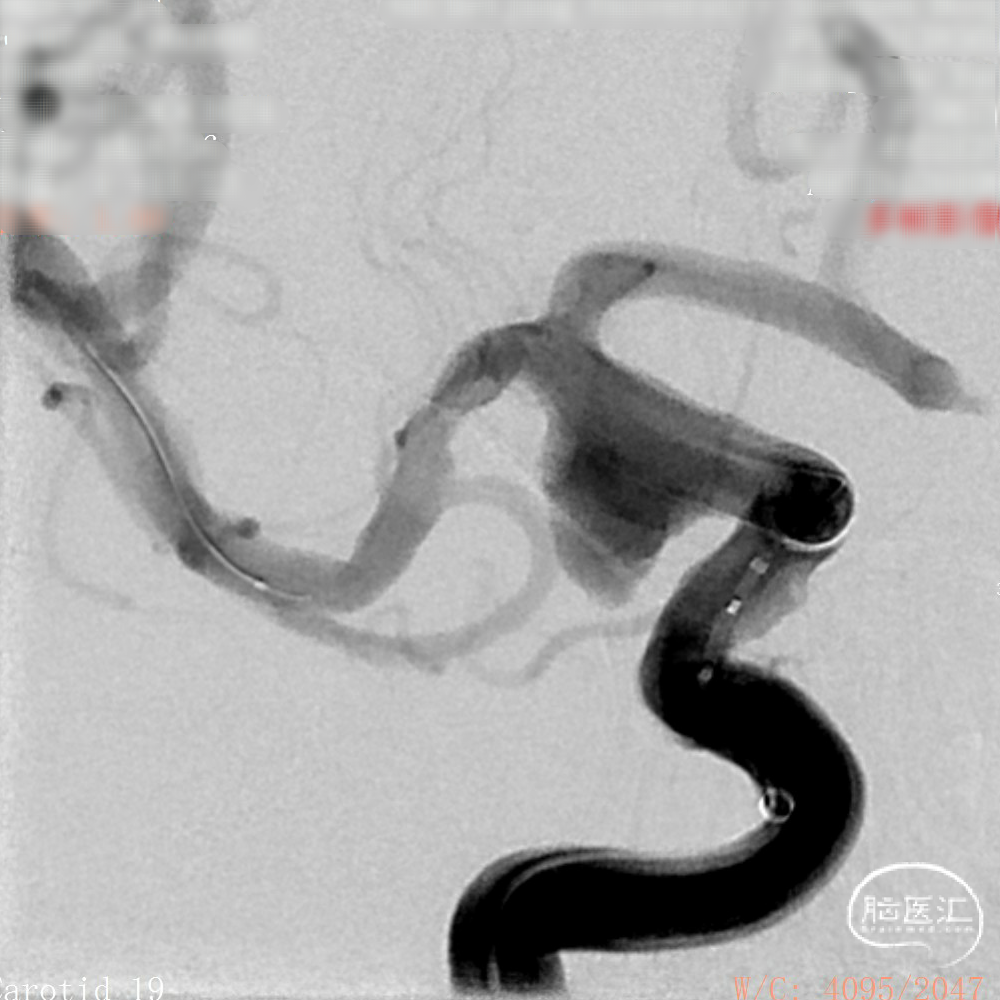

DSA造影:

工作角度:

正侧位造影:支架放置后可见动脉瘤内造影剂明显滞留。